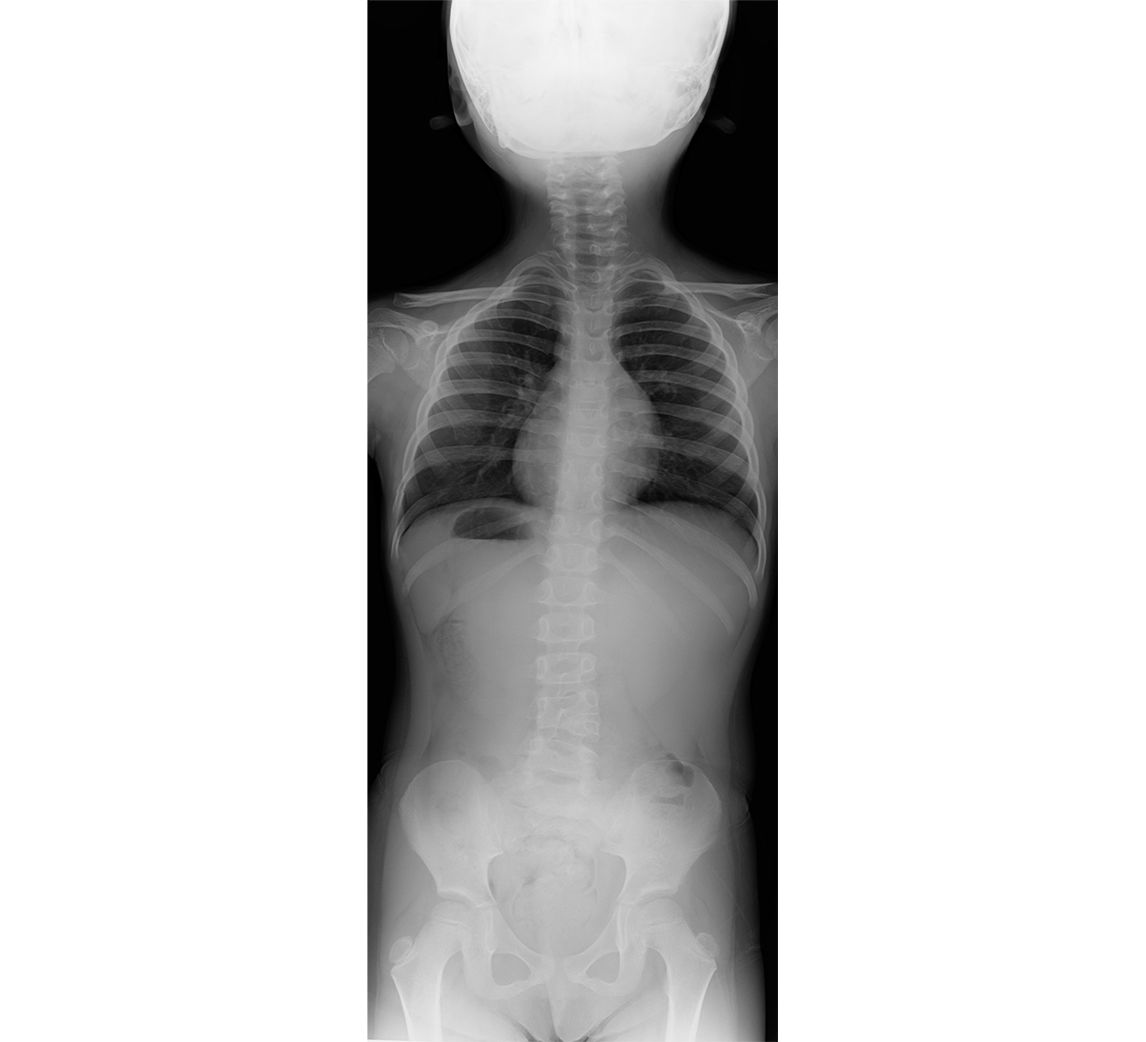

思春期特発性側弯症、立位全脊柱X線正面像

13歳女性、T6-L1でCobb角58°の側弯を認める。